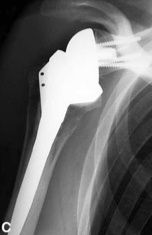

There are

anatomical prostheses and

reversed prostheses - the choice is made depending on well-defined criteria

Reversed shoulder prosthesis Anatomical shoulder prosthesis